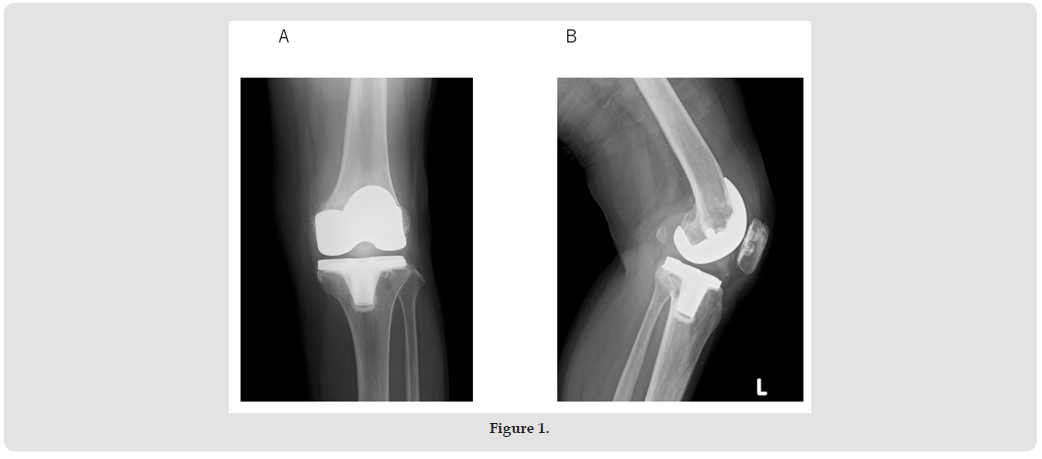

A 77-year-old woman with osteoarthritis in her left knee underwent Zimmer Persona posterior stabilizer type TKA in another hospital about 3.5 years ago. Three years later, she experienced severe pain and a locking sensation in her left knee while shopping. A swelling and tenderness were observed in the left knee. A joint puncture was then performed. The aspirated fluid resembled blood. The bacterial culture was negative. Subsequently, severe pain and a locking sensation in the knee appeared occasionally. Therefore, she was referred to our department for surgery. Her history was unremarkable. A physical examination revealed swelling and slight local heat of the left knee. Anterior instability was not observed, but varus and valgus instability were eminent. The range of motion (ROM) was 0 to 123o. The knee-rating scale of the Hospital for Special Surgery (HSS) was 53. Radiographs showed that the tibiofemoral joint was not dislocated, and loosening of the implants was not found (Figures 1A & 1B). In the stress radiographs, varus and valgus instabilities (ext. 0o, flex. 30o) were noted (Figures 2A-2D).